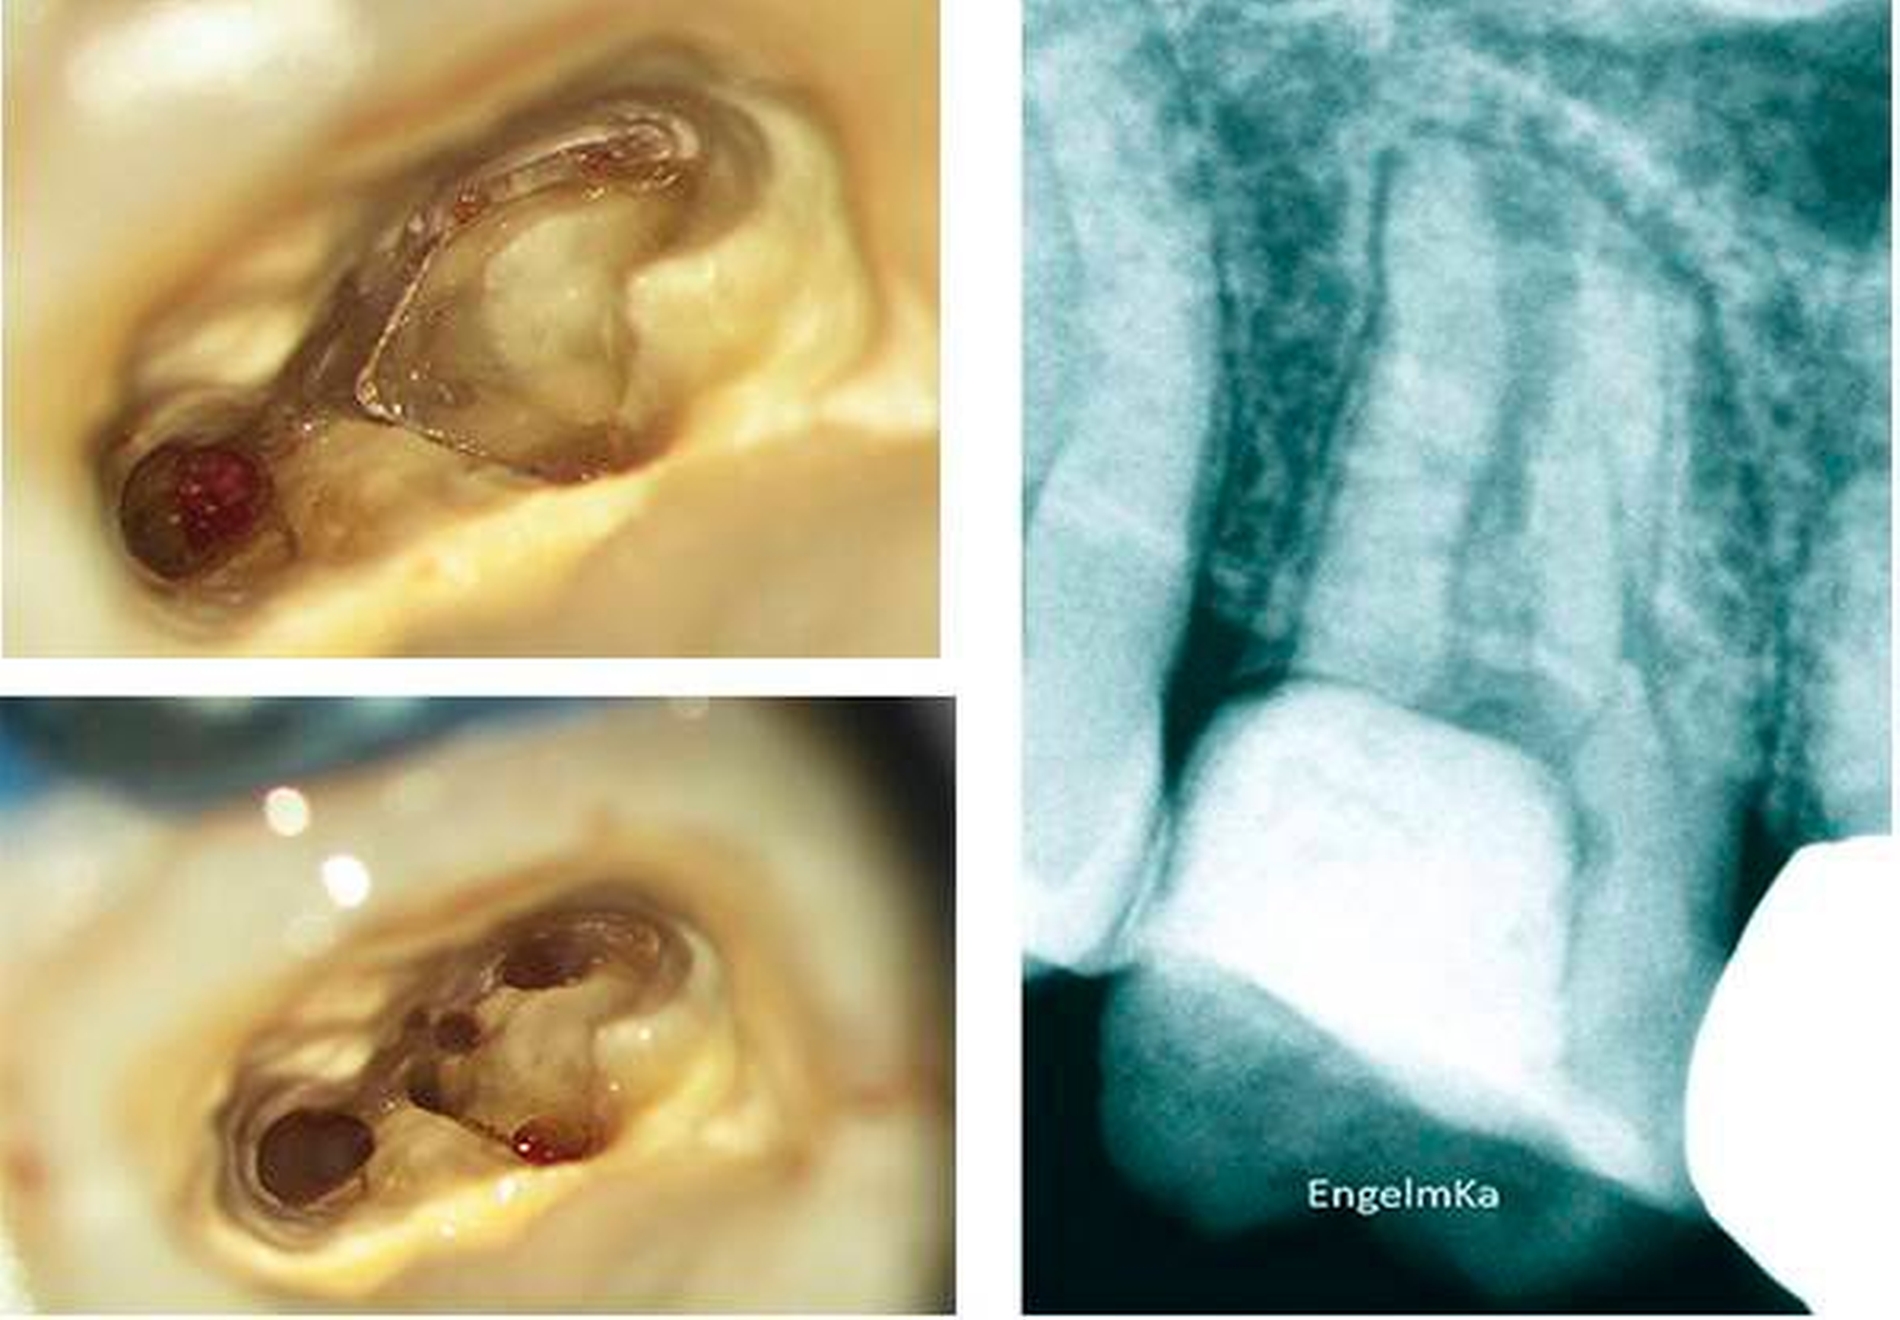

Der Erfolg einer Wurzelkanalbehandlung ist von vielen Faktoren abhängig. Die Voraussetzung für eine suffiziente mechanische und chemische Aufbereitung des Wurzelkanalsystems ist die Präparation einer adäquaten endodontischen Zugangskavität unter aseptischen Bedingungen (Abbildungen 5 und 6).

Während in anatomischen Studien je nach Studiendesign in mehr als 90 Prozent der oberen ersten Molaren vier und mehr Wurzelkanäle nachgewiesen wurden [Kulid & Peters, 1990; Stropko, 1999; Buhrley et al., 2002], gelingt es in den meisten zahnärztlichen Praxen nur mit speziellen Hilfsmitteln, den zweiten Anteil des mesiobukkalen Wurzelkanalsystems systematisch und reproduzierbar darzustellen und mechanisch zu erweitern. Infolgedessen wird von einem seltenen Behandlungsfall ausgegangen, wenn ein vierter Wurzelkanal mechanisch vollständig erweitert wurde. Tatsächlich handelt es sich jedoch um ein Ergebnis unzureichender optischer Vergrößerung und fehlender Ausleuchtung [Buhrley et al., 2002; Schwarze et al., 2002]. Der seltene Fall ist aber vielmehr das Auftreten von weniger oder mehr als vier Wurzelkanälen in einem dreiwurzeligen oberen ersten Molaren [Moral, 1915; Stropko, 1999].

Abweichend von der typischen Wurzelform eines dreiwurzeligen Molaren können auch ein-, zwei-, vier- oder fünfwurzelige Molaren beobachtet werden (Abbildung 2). Weitere akzessorische Wurzelkanäle können – bedingt durch die Produktion von Sekundär- und Tertiärdentin – sowohl in der mesiobukkalen Wurzel als auch in der distobukkalen oder in der palatinalen Wurzel auftreten (Abbildungen 10 und 11).